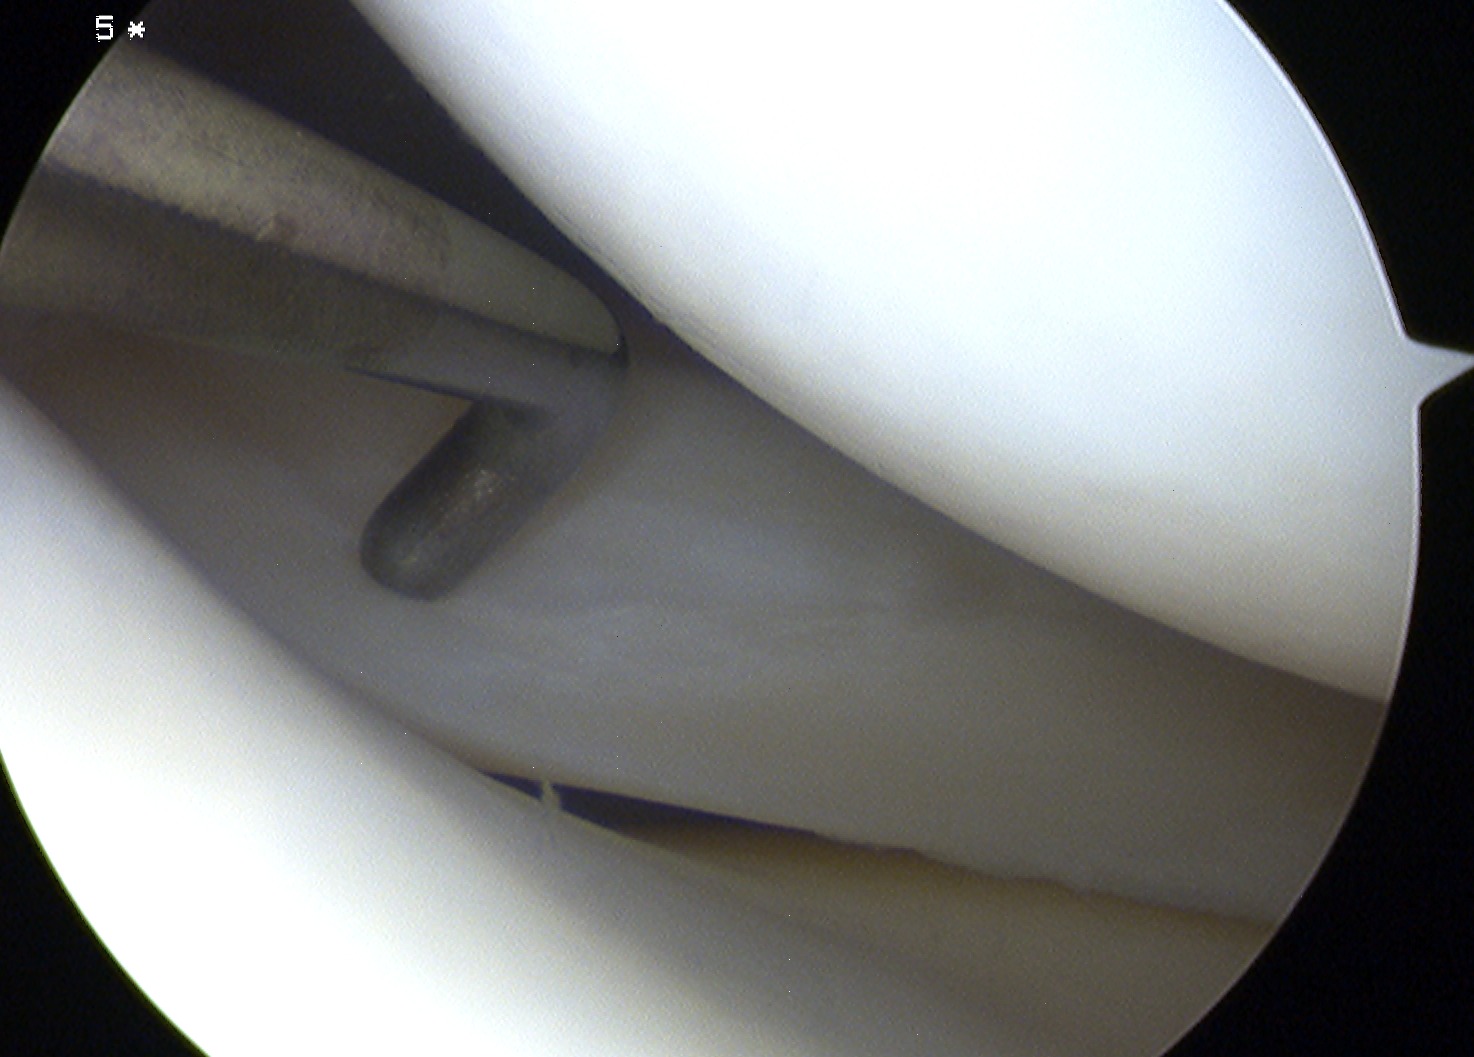

Arthroscopy

Mainstay of diagnosis and treatment

Surgical Indications

Painful locking / clicking with disability

Acutely locked knee

Repairable meniscus in combination with ACL injury

Repairable meniscal injury in young

Options

1. Leave / non operative treatment

2. Excise

3. Repair

4. Meniscal transplant